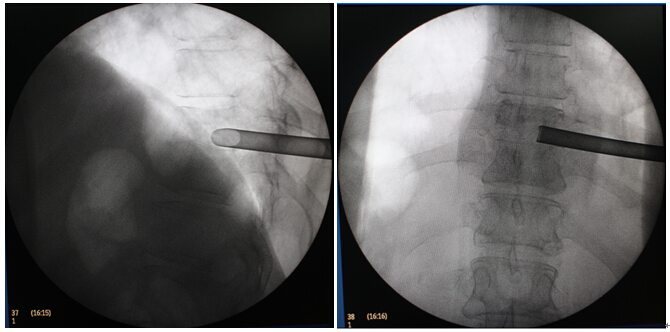

体表定位                            成功置入工作通道

置入通道后透视